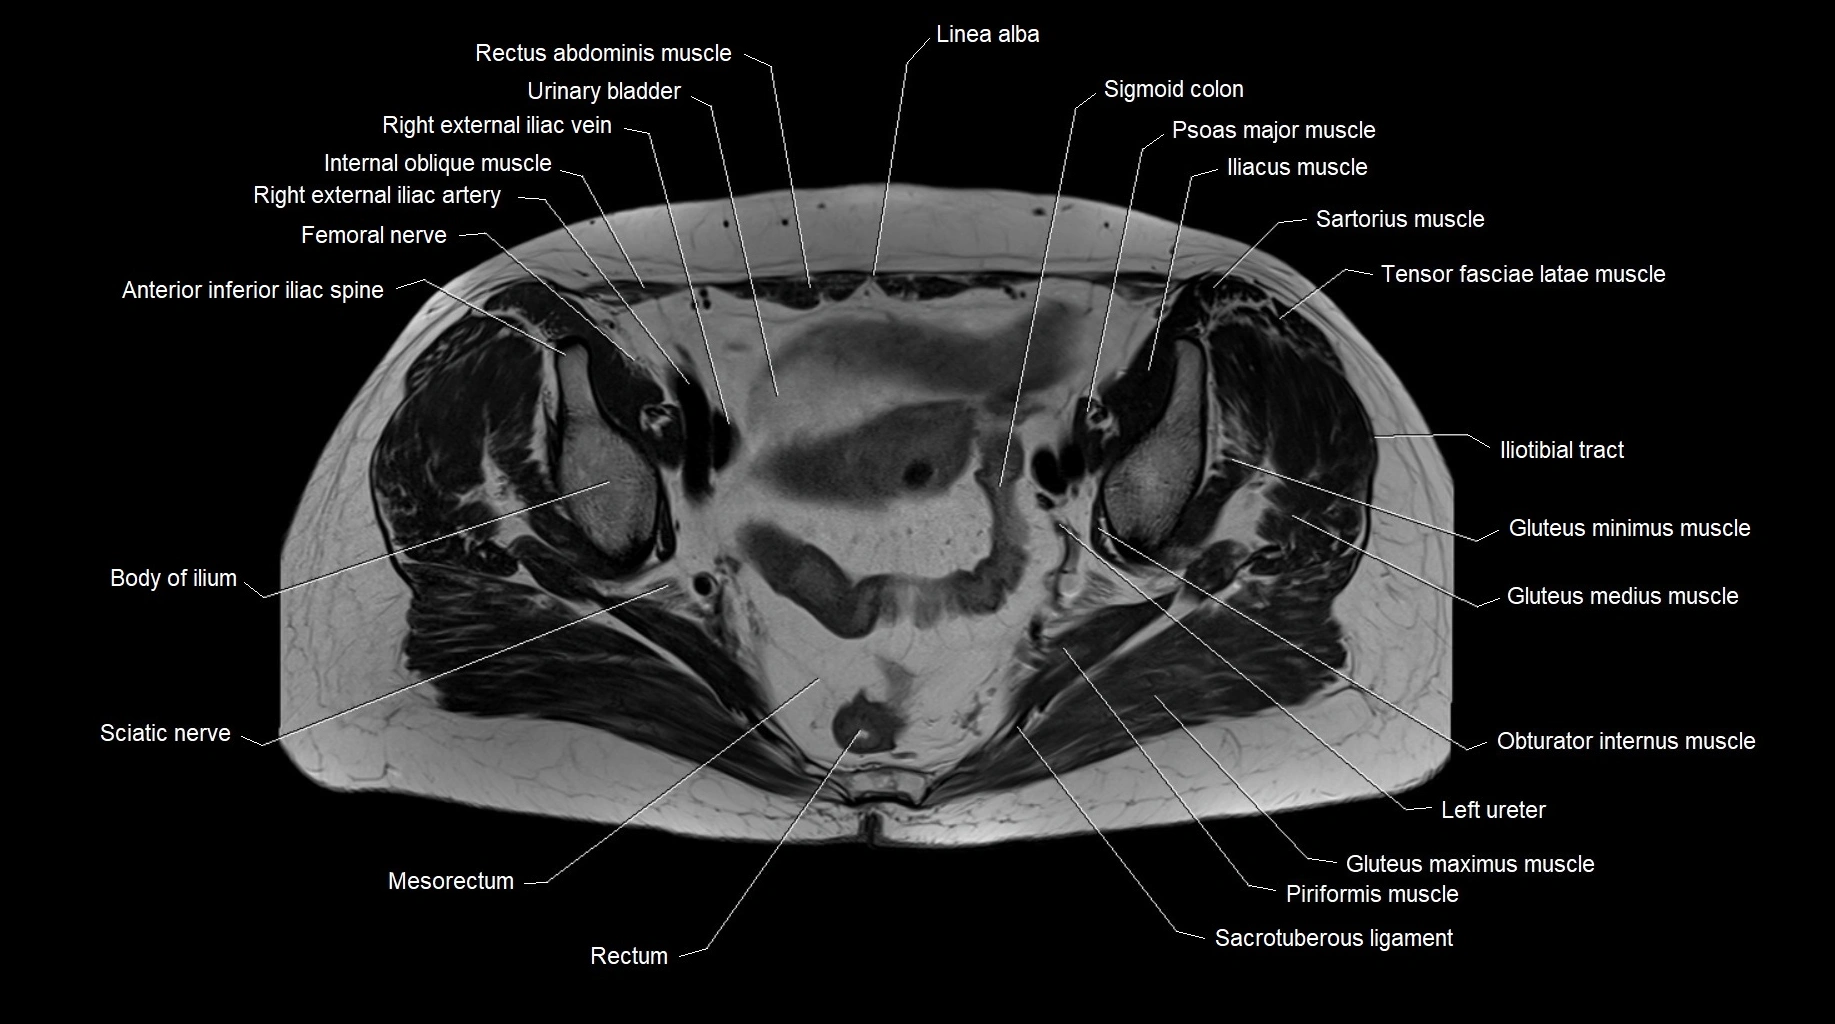

MRI images